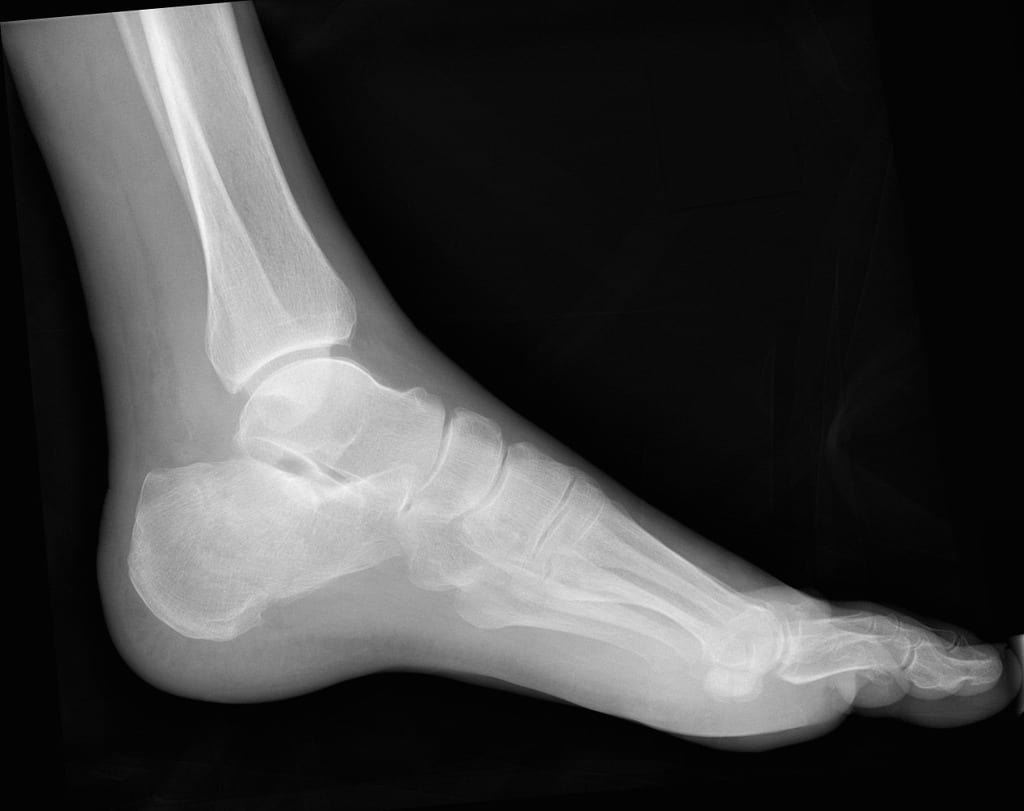

How Do You Fix A Broken Heel . Surgical treatment of calcaneus fractures usually involves making an incision over the outside of the foot and placing a metal plate and screws into the broken heel bone. The foot can be placed in a split or a removable fracture boot so that patients can. The bone takes about three to four months to heal either way. In general, patients whose normal heel anatomy is restored have better outcomes, and in most cases, recreating the normal heel anatomy involves surgery. You may need surgery to repair a heel fracture so you can use your foot again. Usually, treatment involves wearing a cast or splint and avoiding putting weight on your heel for up to eight weeks. During surgery, the surgeon moves the pieces of bone back into place. In most instances, if you’re simply. Your healthcare provider will attempt to restore the normal alignment of the bone and return the cartilage surface as close to normal as possible. Some heel fractures can be treated without surgery. Treating for a bruised heel and a calcaneal fracture are similar, but they can vary based on how the area responds to treatment. Because most calcaneus fractures cause the bone to widen and shorten, the goal of treatment is to restore the normal anatomy of the heel. Some broken heel bones need surgery, but others don't. The surgeon then puts in metal. If you don't need surgery, you'll still need to limit movement and.